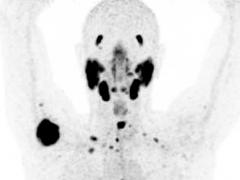

PSMA-PET: aanwinst voor de prostaatkankerdiagnostiek